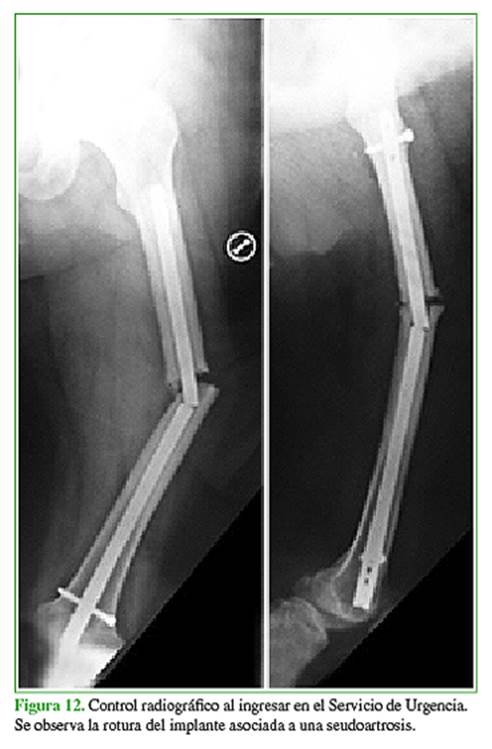

A los dos años del accidente, ingresó en el Servicio de Urgencia con dolor y dificultad para caminar, sin un antecedente traumático. Se observó una seudoartrosis asociada a la rotura del clavo endomedular (Figura 12).